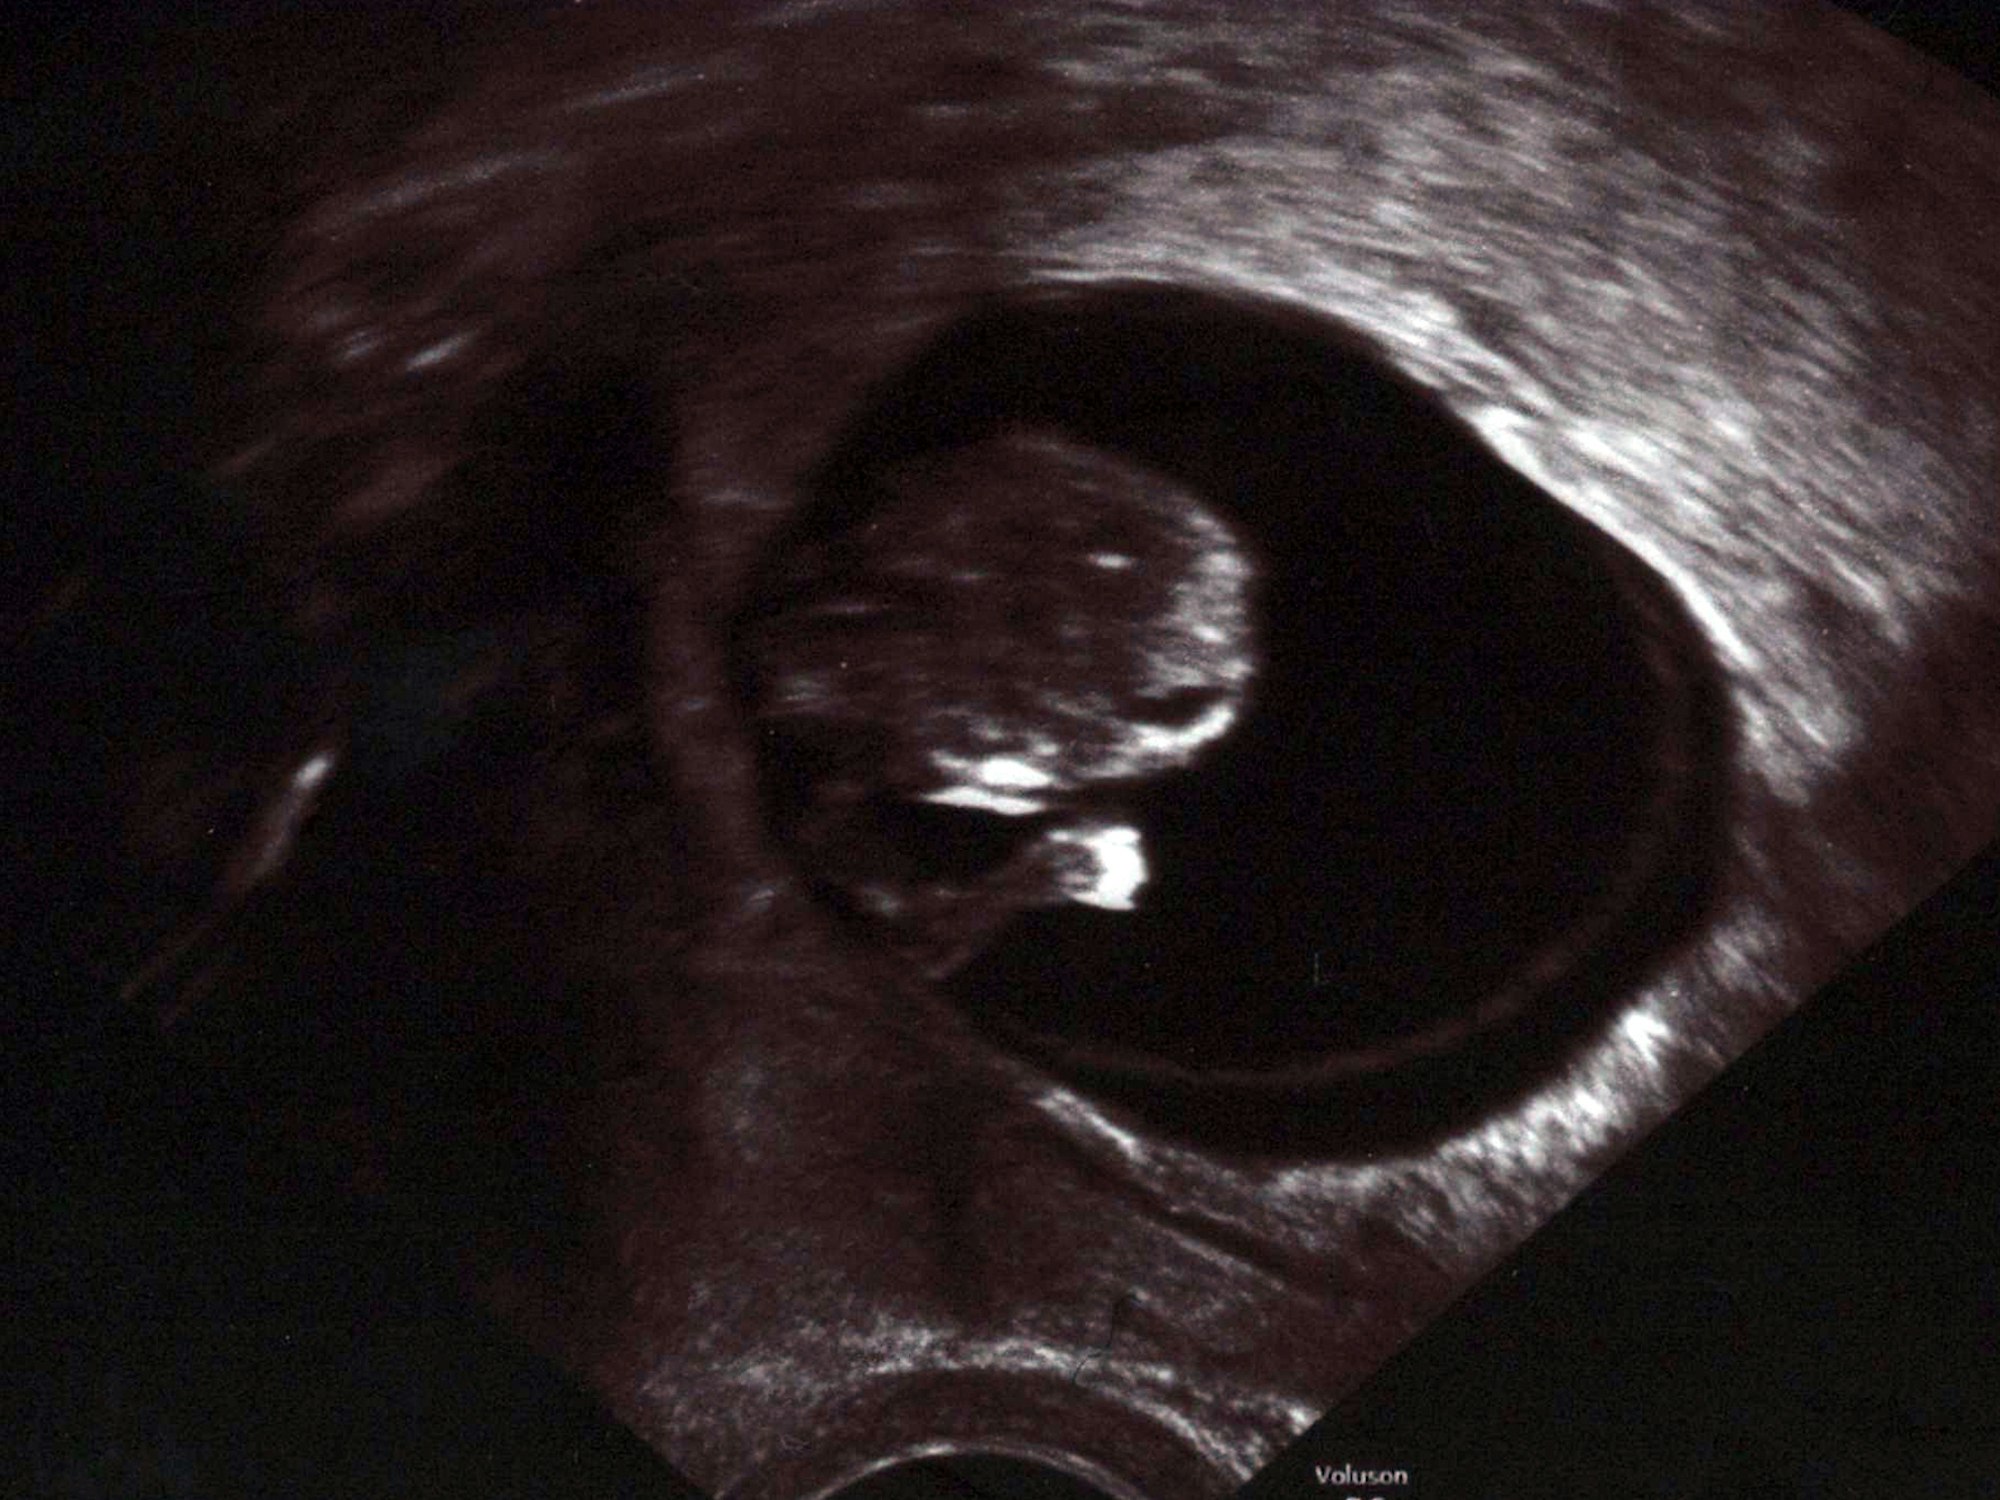

Eine schwangere Mutter schaut sich das Ultraschallbild ihres Kindes an.

Schon in der 10. Woche ist das Ungeborene deutlich zu erkennen und man kann seinen Herzschlag auf dem Ultraschallgerät sehen.